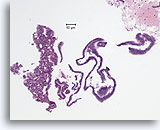

Papillair carcinoom, Borst FNA, Celblok.

Een kleine versterking van het ThinPrep® in afbeelding 51-52 toont een duidelijke papillaire configuratie met een monotone stratificerende populatie.

10X

Papillair carcinoom, Borst FNA, Celblok.

Een kleine versterking van het ThinPrep® in afbeelding 51-52 toont een duidelijke papillaire configuratie met een monotone stratificerende populatie.

10X

Papillair carcinoom, Borst FNA, Celblok.

De afwezigheid van een immunokleuring met calponine duidt op een diagnose van een papillair carcinoom.

40X

Papillair carcinoom, Borst FNA, Celblok.

De afwezigheid van een immunokleuring met calponine duidt op een diagnose van een papillair carcinoom.

40X

Papillair carcinoom, Borst FNA, Celblok.

De afwezigheid van kleuring met p63 helpt een papilloom uit te sluiten.

40X

Papillair carcinoom, Borst FNA, Celblok.

De afwezigheid van kleuring met p63 helpt een papilloom uit te sluiten.

40X

Papillair carcinoom, Borst FNA, Celblok.

De papillaire kern is bekleed met vrij stratificerende ductale cellen en er zijn geen myoepitheliale cellen.

40X

Papillair carcinoom, Borst FNA, Celblok.

De papillaire kern is bekleed met vrij stratificerende ductale cellen en er zijn geen myoepitheliale cellen.

40X

Papillair carcinoom, Borst FNA, Celblok.

Let op de afwezigheid van myoepitheliale cellen in het epitheel dat de fibrovasculaire kern bedekt.

40X

Papillair carcinoom, Borst FNA, Celblok.

Let op de afwezigheid van myoepitheliale cellen in het epitheel dat de fibrovasculaire kern bedekt.

40X